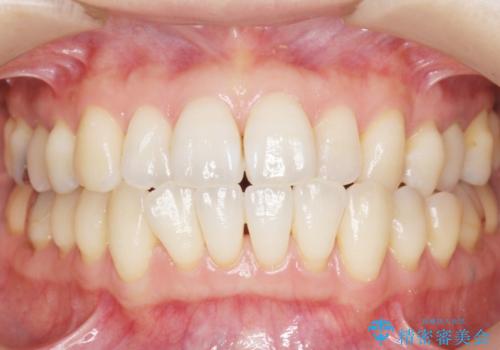

自然な見た目と咬み心地にご満足頂けました。

オフィスホワイトニングを行い、白くなった天然歯に合わせたシェード(お色味)でクラウンを作製しました。

モチベーションが上がり、他の銀歯もセラミックで治していきたいとご希望され、現在治療中です。

クラウンの種類:オールセラミッククラウン スタンダード